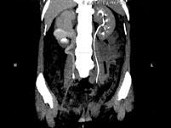

- 多项选择题女,44岁, 突发性胁腹部绞痛并向会阴部放射伴血尿一次,CT扫描如图所示, 下列说法正确的是 ( )

A、右侧肾盂肾盏扩张

B、右输尿管中上段扩张

C、右输尿管内可见沿输尿管走行的高密度影

D、右输尿管结石

E、左肾输尿管未见异常